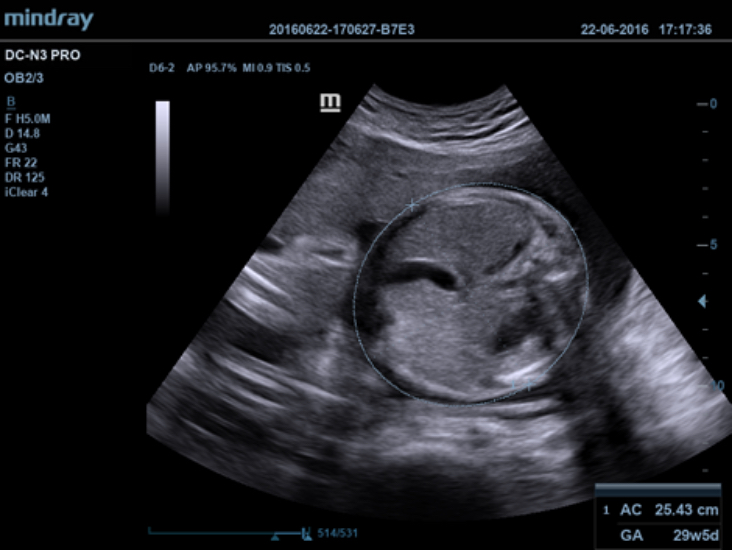

El DC-N3 PRO es la respuesta a sus requisitos de alta calidad de la imagen, versatilidad y asequibilidad. El DC-N3?PRO es el mejor equipo en su clase y es realmente una redefiniciĂłn de los principios bĂĄsicos que le brinda mucho mĂĄs que tan solo un sistema ecogrĂĄfico normal. Con caracterĂsticas avanzadas y el precio mĂĄs competitivo de la industria, se trata de ayudarlo a elevar sus expectativas.

El DC-N3 PRO es un sistema Doppler a color con todas las funciones que satisface sus necesidades de diagnĂłsticos mĂĄs rĂĄpidos, confiables y precisos. Gracias al mejor rendimiento, eficacia y dise?o de su clase, puede estar seguro de que obtendrĂĄ una experiencia de ecografĂa excepcional. Con su dise?o compacto, fĂĄcil de usar y ergonĂłmico, se puede mover, usar y ubicar segĂșn sus requisitos sin lĂmites.